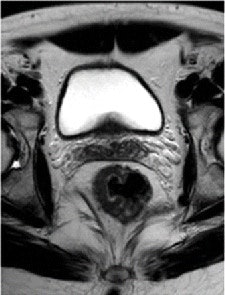

Pre- and post-treatment MRI was performed with a 1.5-tesla system (Intera R10, Philips Healthcare) using an eight-element pelvic phased-array surface coil. The subjects were imaged in the prone position after the placement of a thin rectal catheter in the rectum.

After initial localization imaging, researchers acquired MR images of the pelvis and rectum, with T2-weighted images obtained in the transverse, coronal, and sagittal planes during the scanning time of approximately 30 minutes.

The MR images calculated the mean tumor volume was 58 cm3 ± 75 before chemotherapy/radiation treatment and 20 cm3 ± 31 after therapy. The mean tumor volume reduction ratio in all patients was 68% ± 23.